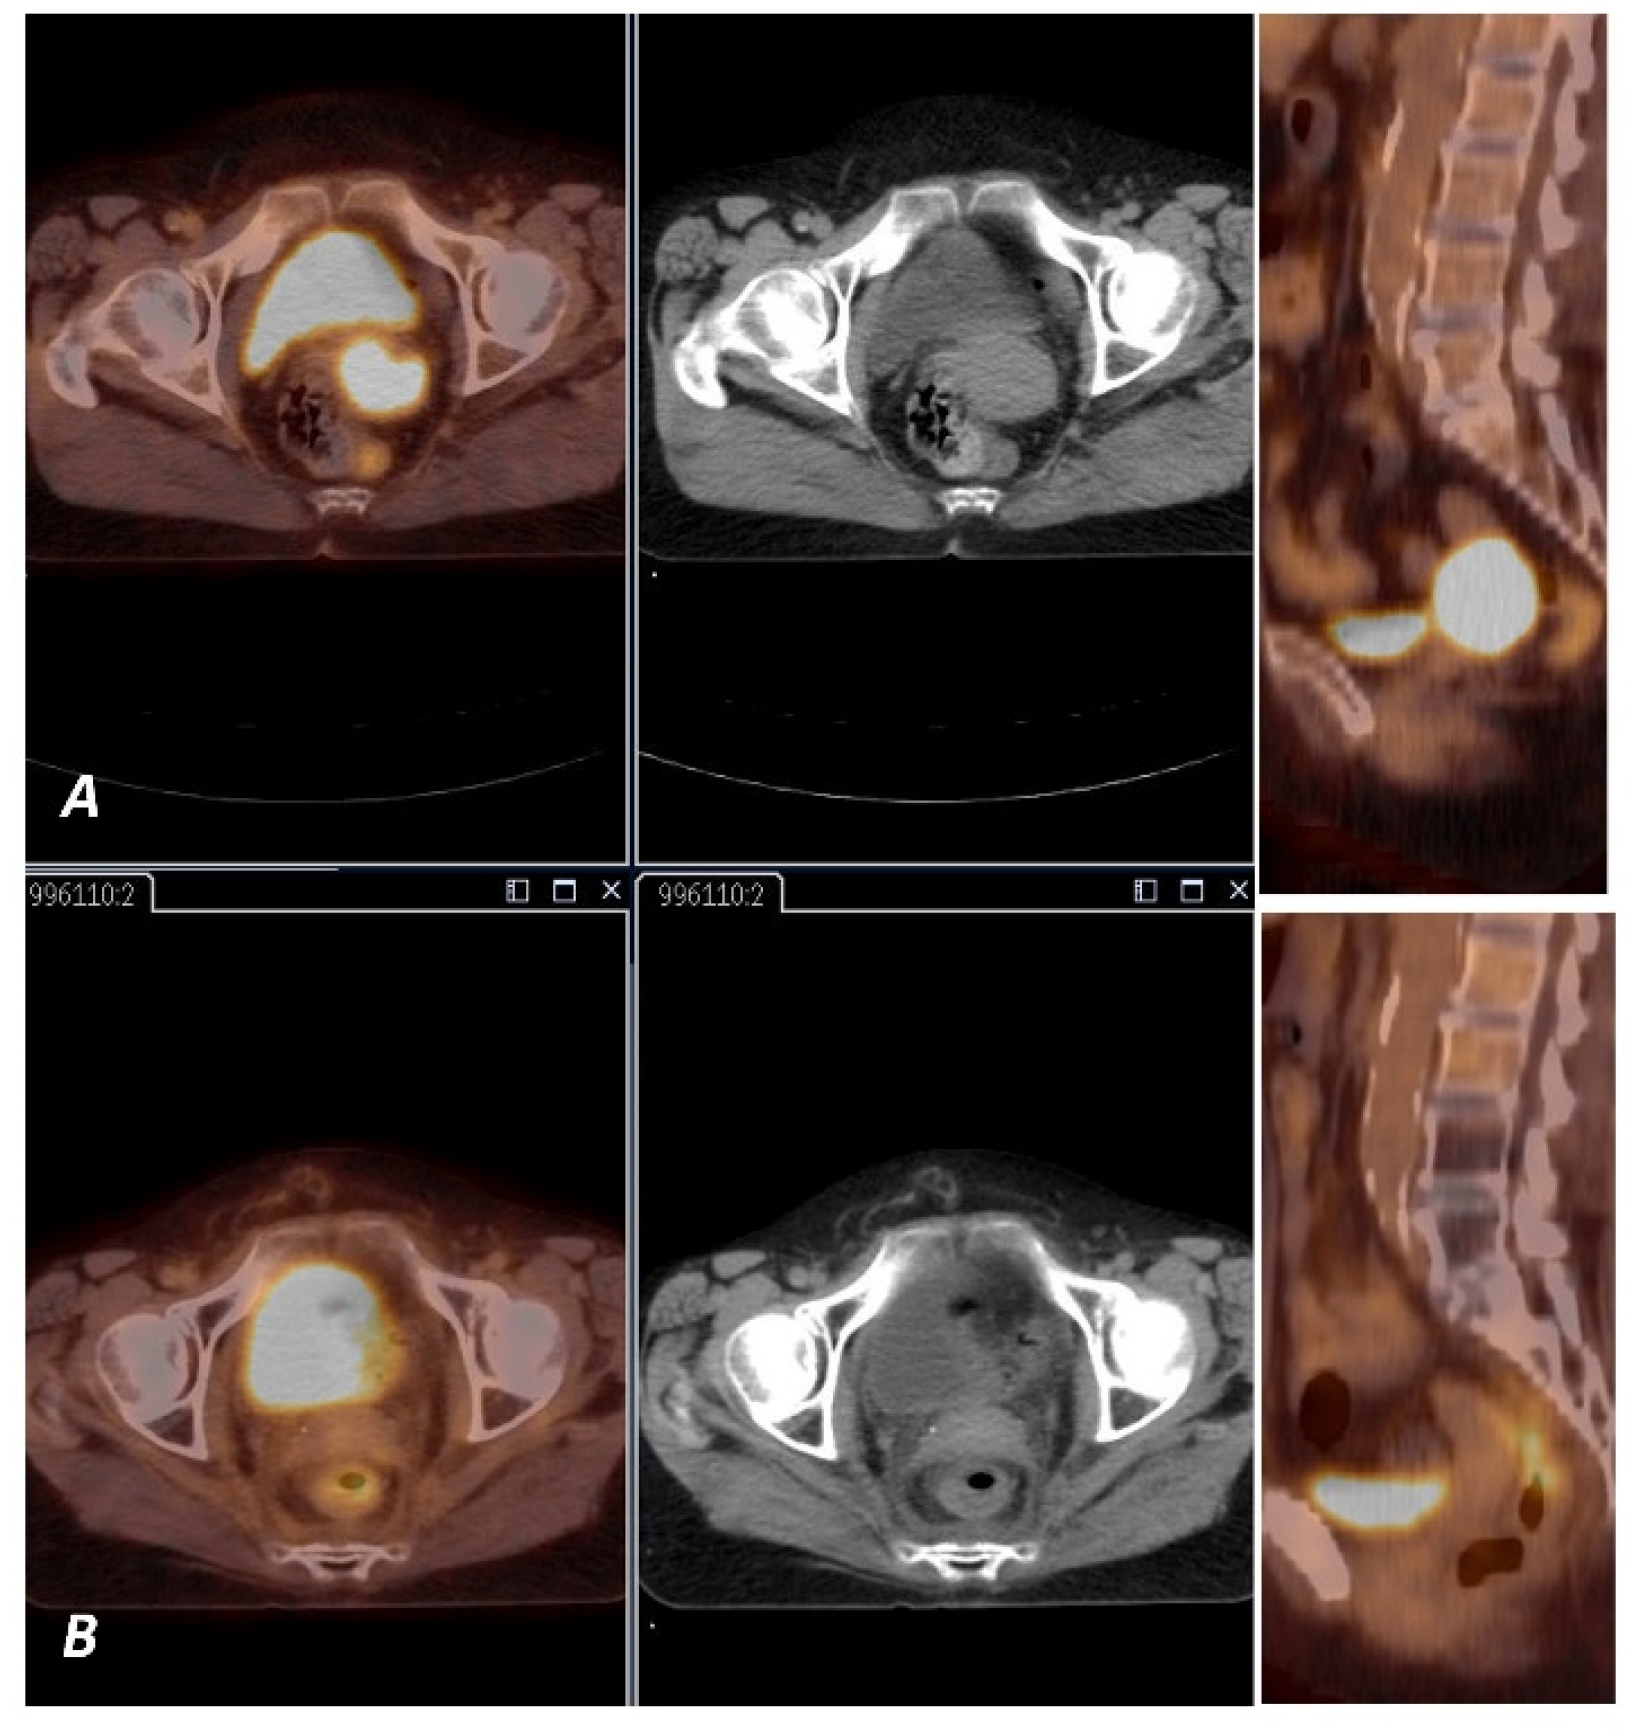

2.2. PET Imaging and Analysis